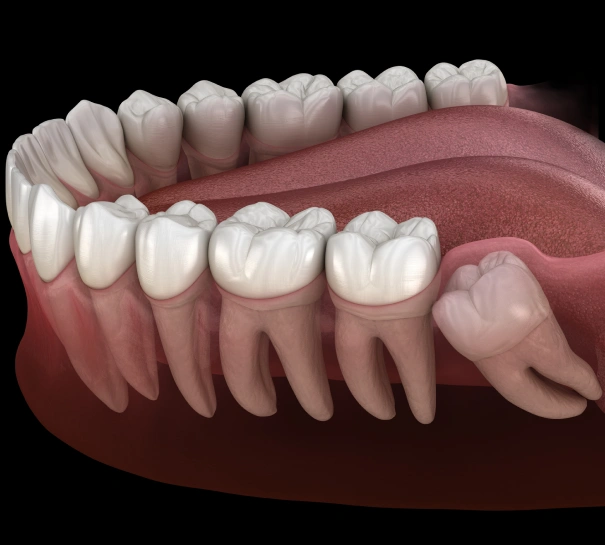

Wisdom teeth are the last set of molars to appear, often coming in during the late teens or early twenties. For some people, these teeth emerge without problems. For many others, however, wisdom teeth grow in at awkward angles, push against neighboring teeth, or remain trapped beneath the gums. These issues can cause pain, infection, and even long-term damage to your bite.

On the day of the procedure, anesthesia or sedation may be offered to keep you comfortable. The type depends on your needs and the complexity of the case. Once the area is fully numb, your dentist or oral surgeon carefully removes the tooth. Impacted teeth may require a small incision, while teeth that have already erupted are generally easier to remove.